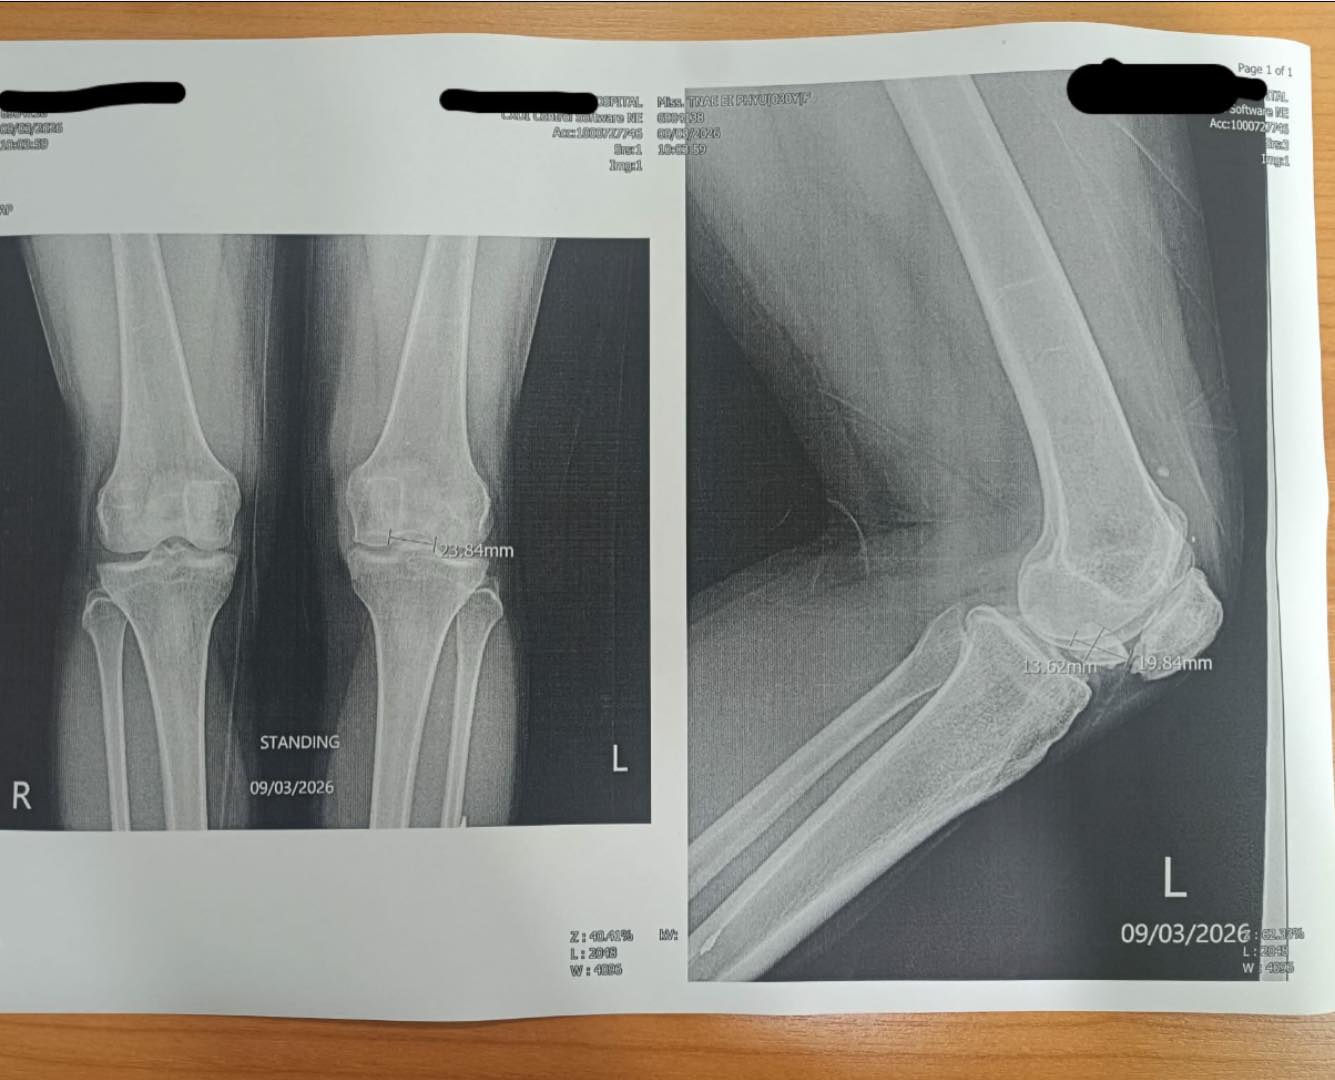

今回は、チェンマイ在住のフリーランス記者の手術費に10万円支援させていただきました。記者は取材中左脚を砲弾の破片で傷つけ、直ぐに手術をしなければ歩けなくなる状況になっていました。現地で危険に晒されながらも、懸命に取材を続けられた勇気と努力に敬意を表すとともに一日でも早い回復をお祈り申し上げます。